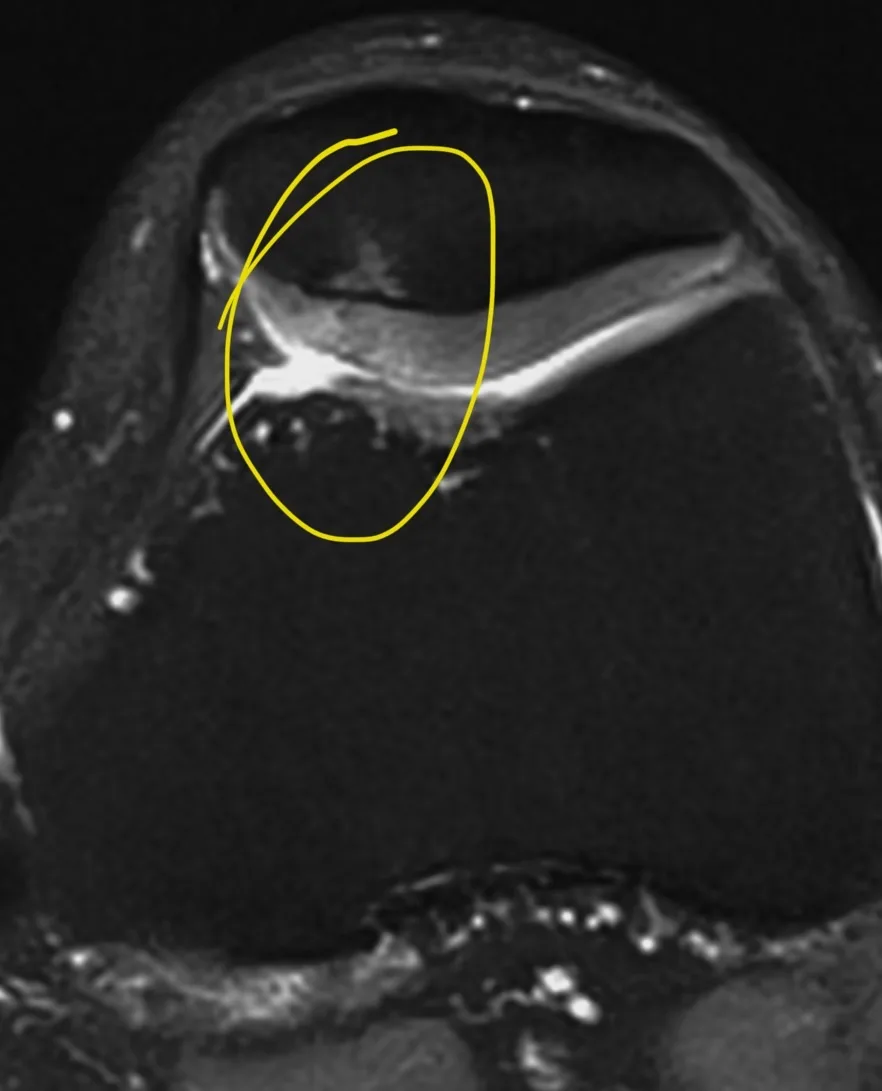

А вот вдогонку ещё костное повреждение Банкарта, парень 20 лет. Последствия переднего вывиха плеча.

Из-за отрыва сухожилия подлопаточной мышцы вывихнулось медиально сухожилие длинной головки бицепса. Сухожилие подлопаточной мышцы является одновременно удерживателем длинной головки бицепса в межбугорковой борозде, вплетаясь в малый бугорок плеча и как бы продолжаясь в поперечную связку (связку Броди), которую некоторые считают не истинной связкой, а частью сухожилия надостной мышцы.